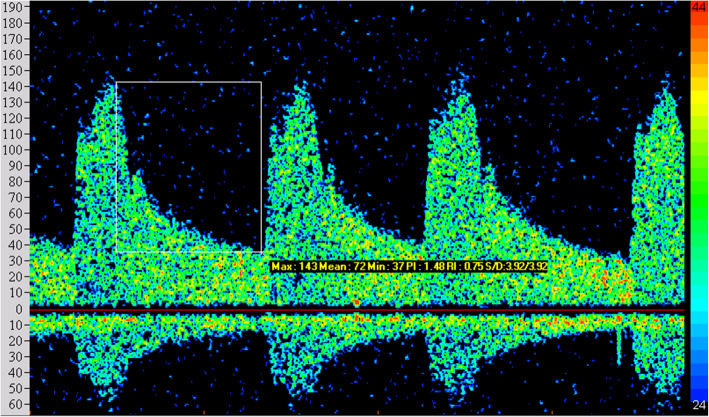

The abnormal rate of TCD in observation group was 93.75% (75/80). The main characteristics were that the blood spectrum was similar to a right triangle, the peak time was delayed and waveform was blunt, the flow velocity on both sides was unbalanced, PI showed a decreasing or increasing trend, the abnormal frequency spectrum S1 ≤ S2, and the image comparison between observation group and control group is shown in Figs. 1 and 2. The peak velocity of MCA, ACA, PCA, and VA in the left and right sides of the observation group were higher than those in the control group, while BA was lower than that in the control group, with a statistically significant difference (P < 0.05). Refer to Table 2.

Fig. 1.

Blood flow spectrum of the control group in TCD examination

Fig. 2.

Blood flow spectrum of the observation group in TCD examination